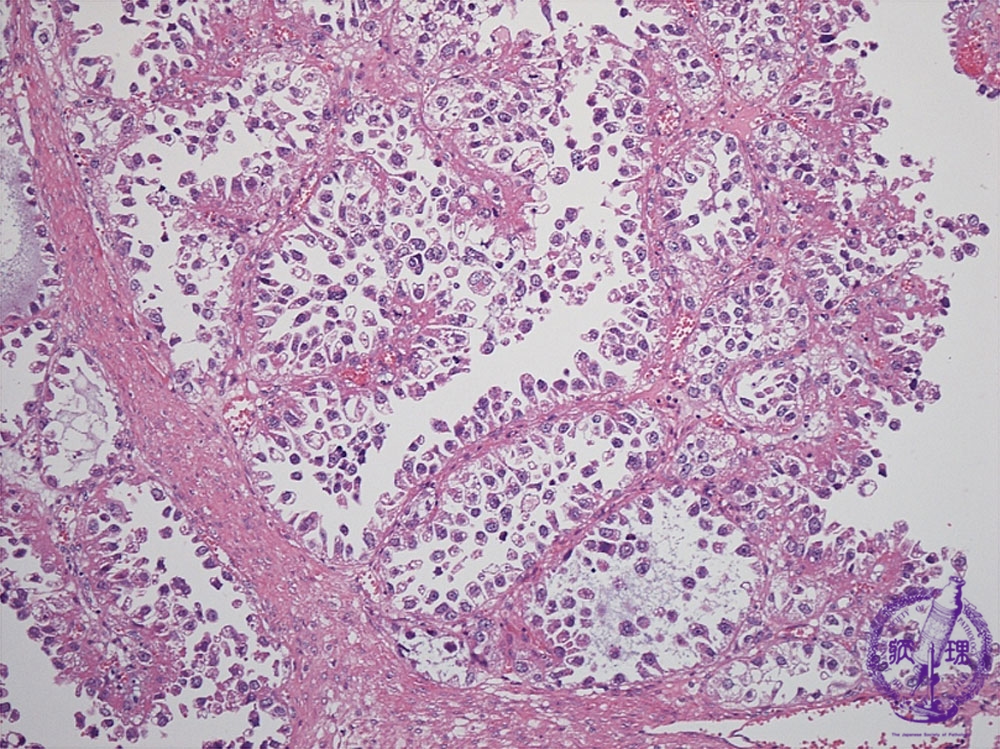

Histology (HE stain, intermediate power): Carcinoma cells with clear cytoplasm proliferated in papillary or tubular structure.